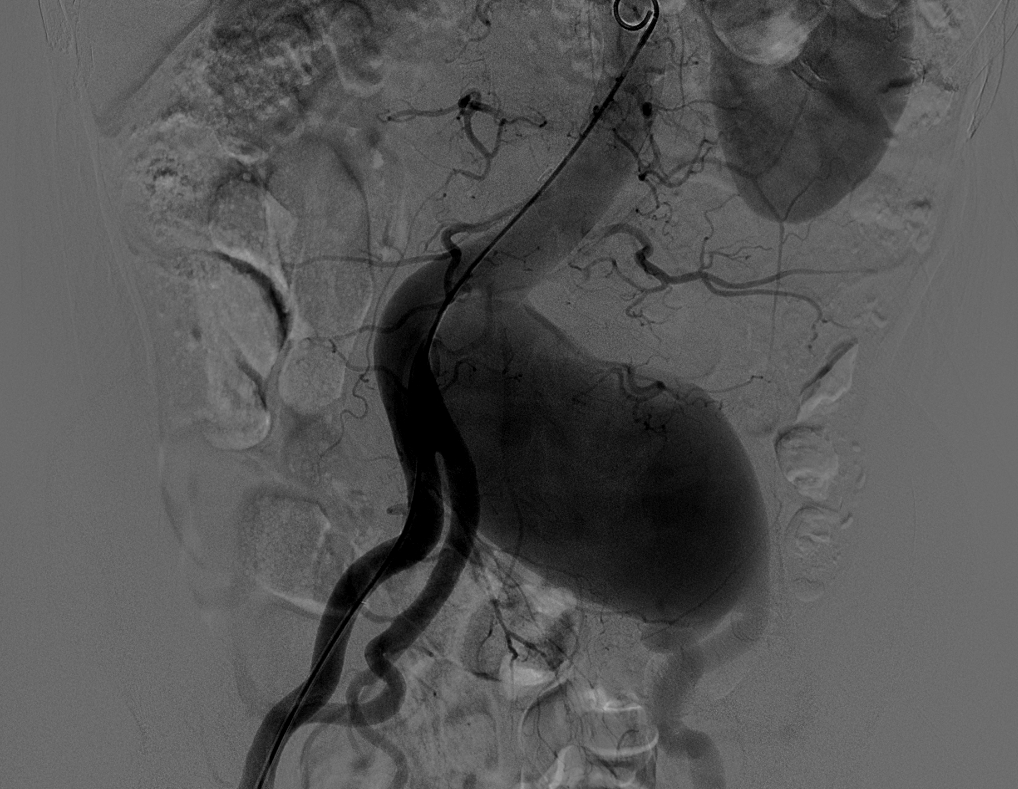

2015年1月15日我院普通外科血管专业组贾玉龙主任医师、汪岩副主任医师及汪鑫住院医师等成功为一巨大髂动脉瘤患者完成了微创手术治疗。患者男性,56岁,承德人,发现下腹部搏动性包块并有疼痛感,于当地医院就诊发现左髂总动脉巨大动脉瘤,当地医院无法治疗此病,遂来我院就诊,经检查发现其左髂总动脉有约10X6X6cm3巨大动脉瘤。

髂动脉扩张性病变直径至少较正常动脉扩大50%即可谓髂动脉瘤,髂总动脉扩张性病变直径大于1.5cm即可称髂总动脉瘤。临床上所见的髂动脉瘤大多数是延续于腹主动脉瘤,位于髂动脉部位包括髂总、髂外和髂内动脉的动脉瘤,而不伴有腹主动脉瘤,称为孤立性髂动脉瘤,临床少见。此例如此巨大,更为罕见。孤立性髂动脉瘤的常见发病部位是髂总动脉和髂内动脉,髂外动脉少见。孤立性髂动脉瘤可以是单发,也可以是多发。动脉瘤破裂出血是孤立性髂动脉瘤高病死率的主要原因,一旦破裂,死亡率高达50%-70%,总体上破裂发生率为14%-70%。通常认为瘤体直径大于3cm破裂风险明显增加,需要手术处理,本例瘤体直径接近7cm。动脉粥样硬化是中、老年人动脉组织结构退行性病变,一旦瘤体形成,只会增大而不会缩小。随着瘤体的增大,可压迫周围组织器官或发生瘤体破裂,目前尚缺乏有效的药物来抑制动脉瘤自然增长、增大的病理过程,也无确切的方法来评估动脉瘤多大以及何时会发生破裂。一旦发现,建议手术治疗。(普外血管组 汪岩)